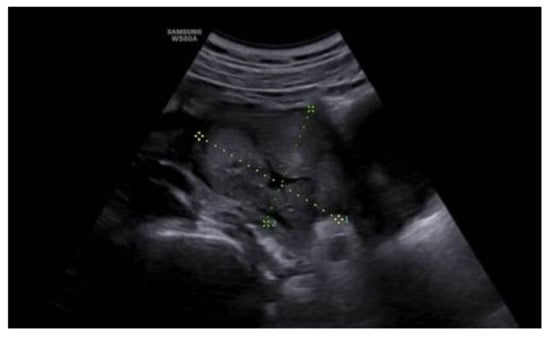

The anatomo-pathological study confirmed the diagnosis of ulcerated aggressive angiomyxoma that affects the deep margin opposite the vaginal mucosa (Figure 7).

The main characteristic of aggressive angiomyxoma in the pathological study is the presence of hypocellular tissue with myxoid stroma in which stellate or spindle cells with elongated cytoplasm with little mitosis and abundant blood vessels are distinguished; this agrees with the anatomopathological findings of the present case.

Figure 7. Hematoxylin–eosin stain.